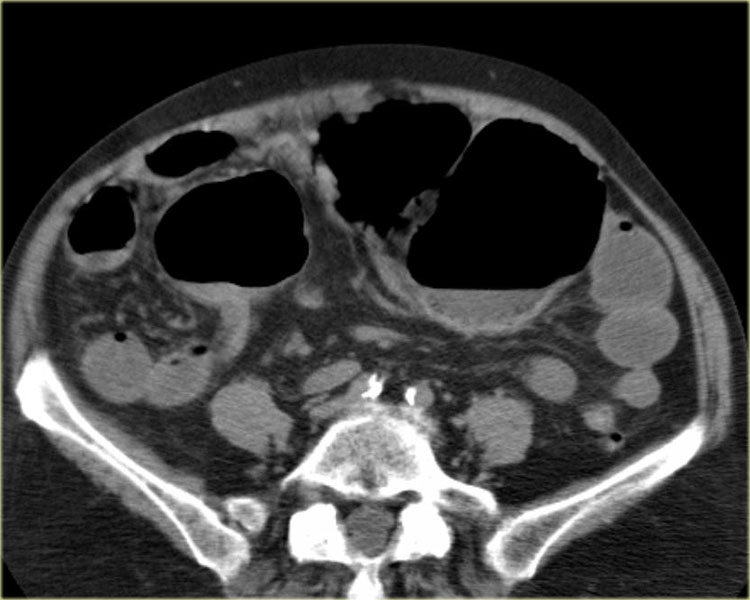

Đây là một trường hợp xoắn đại tràng sigma khác.

Trên X-quang bụng, rất khó nhận biết tình trạng bệnh lý vì có quá nhiều quai ruột giãn.

Lưu ý điểm chuyển tiếp (mũi tên đỏ).